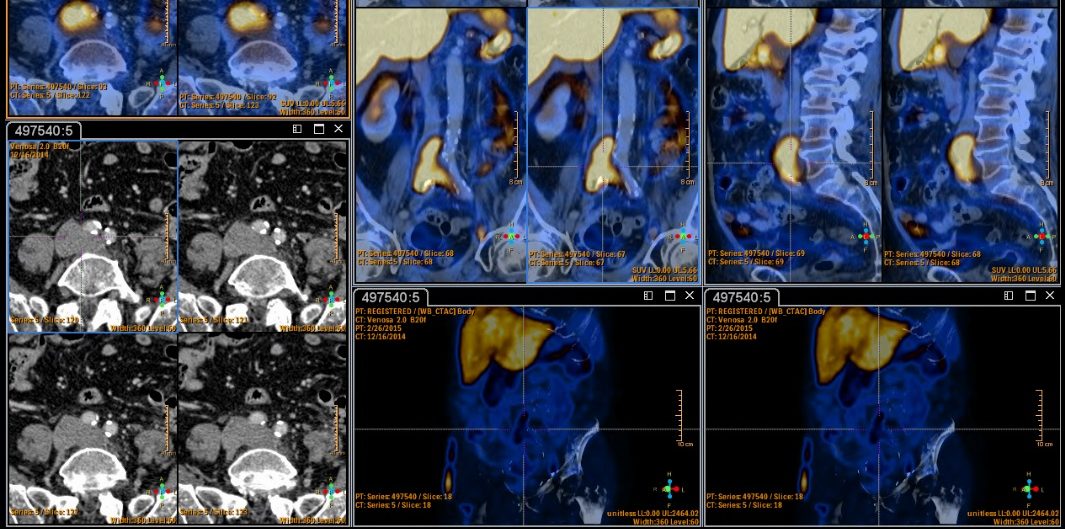

Il corso della ESMIT Winter School è dedicato all’impiego diagnostico dell’Imaging Multimodale: nuovi approcci legati all’impiego di “strumentazioni ibride” ad alto contenuto tecnologico (PET/CT, SPET/CT, MRI/PET), in grado di fornire informazioni morfologiche e metaboliche, associate a sofisticati sistemi informatici che permettono la ricostruzione e la fusione delle immagini e l’analisi dei dati.

L’aggiornamento consentirà ai professionisti di utilizzare nel corso della pratica clinica le più moderne informazioni morfologiche e funzionali al fine di arrivare a una diagnosi, con il vantaggio di migliorare le possibilità di cura e guarigione dei pazienti con patologie oncologiche, cardiovascolari, muscoloscheletriche, neurologiche ed endocrinologiche.

Con multimodalità si intende l’impego integrato di diverse tecnologie di diagnostica per immagini, capaci di produrre informazioni con diverso contenuto biologico e clinico, al fine di raggiungere una maggiore appropriatezza diagnostica e migliore efficienza operativa. La fusione di immagini combina visivamente le informazioni che provengono da diverse strumentazioni per superarne le singole caratteristiche e aumentarne le potenzialità.